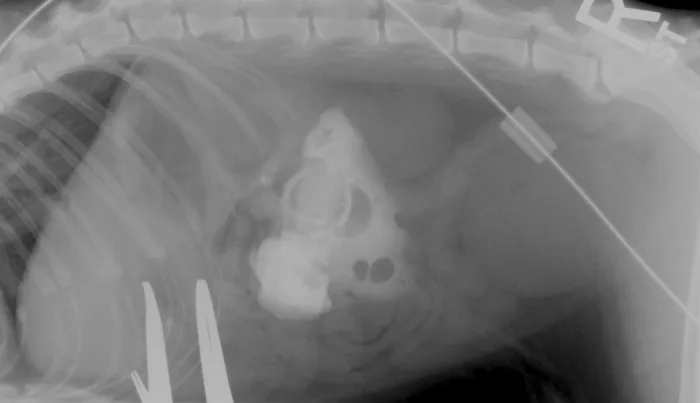

• Figures 3a & 3b. Pre- and postcontrast ventrodorsal radiograph of a cat with low-form gastrostomy tube showing normal positioning of tube in stomach and normal gastrogram without leakage into the peritoneum (Courtesy of Dr. Susan Randell)